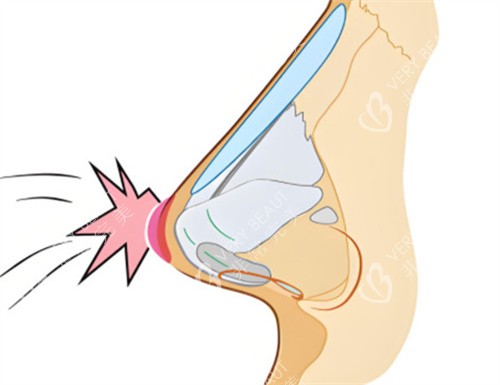

比如,一些患者在初次隆鼻手术后出现了假体移位、感染等问题,导致鼻部形态不佳甚至影响正常功能。

李医生凭借优质的技术,能够精密地取出假体,处理感染部位,并重新塑造出理想的鼻部形态。

但李医生凭借对鼻部解剖结构的深入了解和丰富的临床经验,能够制定个性化的修复方案,更大程度地改善鼻部问题。

在手术过程中,他采用精细的操作手法,尽量减少对鼻部组织的损伤,确保术后修复快,并且能够呈现出自然逼真的结果。

此外,他还会根据患者的自身条件选择合适的材料,如自体软骨等,这些材料与人体组织相容性好,能够更好地融入鼻部,使术后鼻型更加自然。